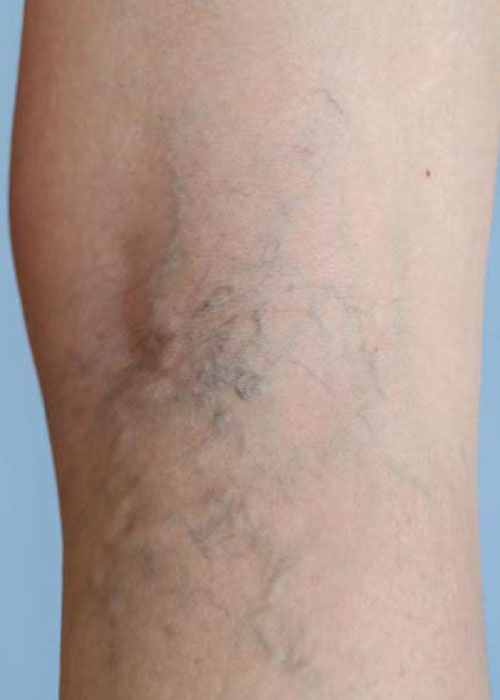

DESCRIÇÃO DO PROBLEMA: VARIZES E TELANGIECTASIAS

As varizes são veias dilatadas e torcidas que geralmente ocorrem nas pernas, resultantes de uma pressão excessiva nas veias, causando um funcionamento inadequado das válvulas venosas. As telangiectasias, por sua vez, são pequenas dilatações dos vasos sanguíneos que se tornam visíveis na superfície da pele, formando manchas vermelhas ou roxas. Ambas as condições estão frequentemente associadas a fatores como: